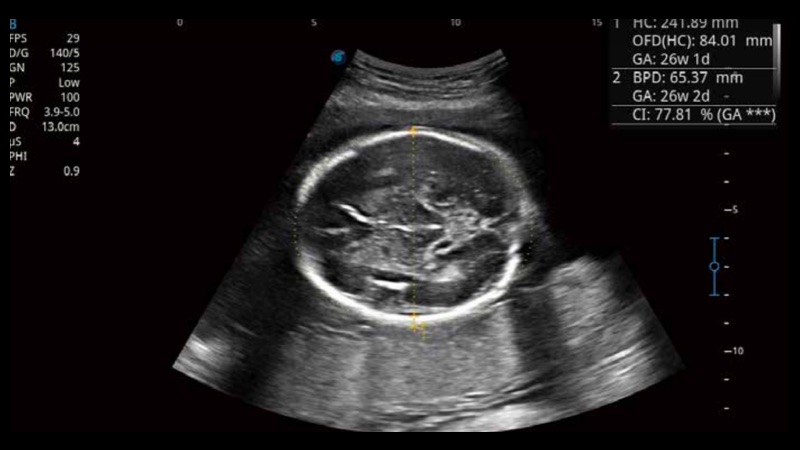

S-Fetus基于大數(shù)據(jù)深度學(xué)習(xí)算法,能夠幫助您在產(chǎn)前篩查過程中智能識(shí)別胎兒標(biāo)準(zhǔn)切面、自動(dòng)測(cè)量并錄入報(bào)告。一個(gè)按鍵,即可智能、精準(zhǔn)、高效地獲取胎兒生理指標(biāo),極大簡化您的產(chǎn)科檢查操作。

可快速對(duì)產(chǎn)科掃查切面完成胎兒生理學(xué)參數(shù)的自動(dòng)測(cè)量,減少操作者按鍵次數(shù),大幅提升檢查效率。

自動(dòng)識(shí)別頸項(xiàng)透明層并獲得NT值,為早孕胎兒畸形篩查提供有效測(cè)量工具,提高診斷效率和診斷信心。